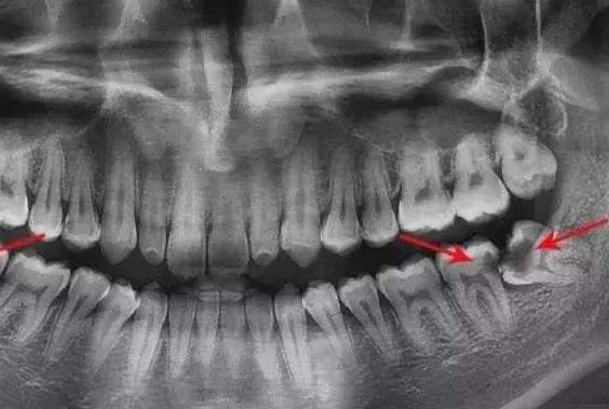

阻生智齿

人类的牙齿是后天长出来的一种骨骼,这种会露出的骨骼并不是一成不变的,有许多人的牙齿在萌发的过程中变歪,而智齿也是如此,变歪的智齿会阻碍和损伤旁边的牙齿,有时甚至会发炎,引起疼痛,所以需要尽快将其拔出。感兴趣的可以了解一下矫正牙齿会导致牙齿松动脱落吗?